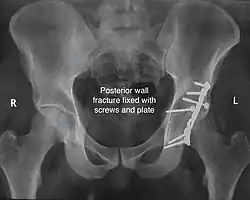

Posterior column and wall fixed using screws and plates

The final management depends on the size of the fragment(s), stability and congruence of the joint. In some cases traction for six to eight weeks may be the only treatment required; however, surgical fixation using screw(s) and plate(s) may be required if the injury is more complex. The latter treatment will be called for if bone fragments do not fall into place, or if they are found in the joint, or if the joint itself is unstable.

Implants : normally lag screws and reconstruction plates are preferred implants